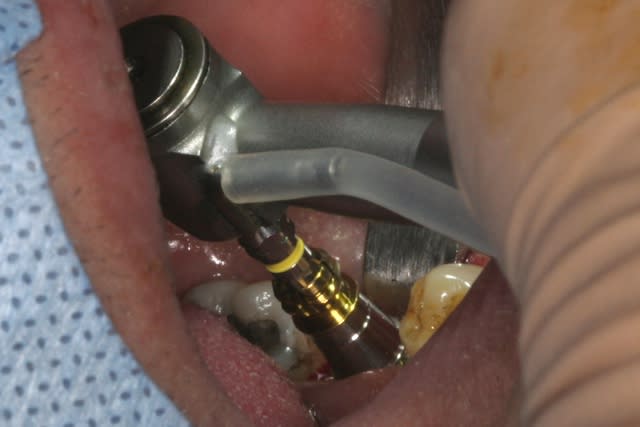

forage, tout ce qu'il y a de plus classique pour ceux qui connaissent ID ou zimmer

pour un implant de 5mm de diamètre on s'arrête au foret de 4.4, passé ici sur 8mm au lieu des 11.5mm car j'étais dans du D3

l'interactive, (t'ain qu'il est beau!!!)

mise en place au CA qui bloque à 45Ncm...on est à 1 ou 2 mm de la crête....pas de problème, on retire le Fm (sympa, la vis, car il y a un filetage dans le Fm, ne risque plus de tomber!!!) et on se reprend direct dans le col de l'implant à la clef à cliquet...comme d'hab quoi...;-)